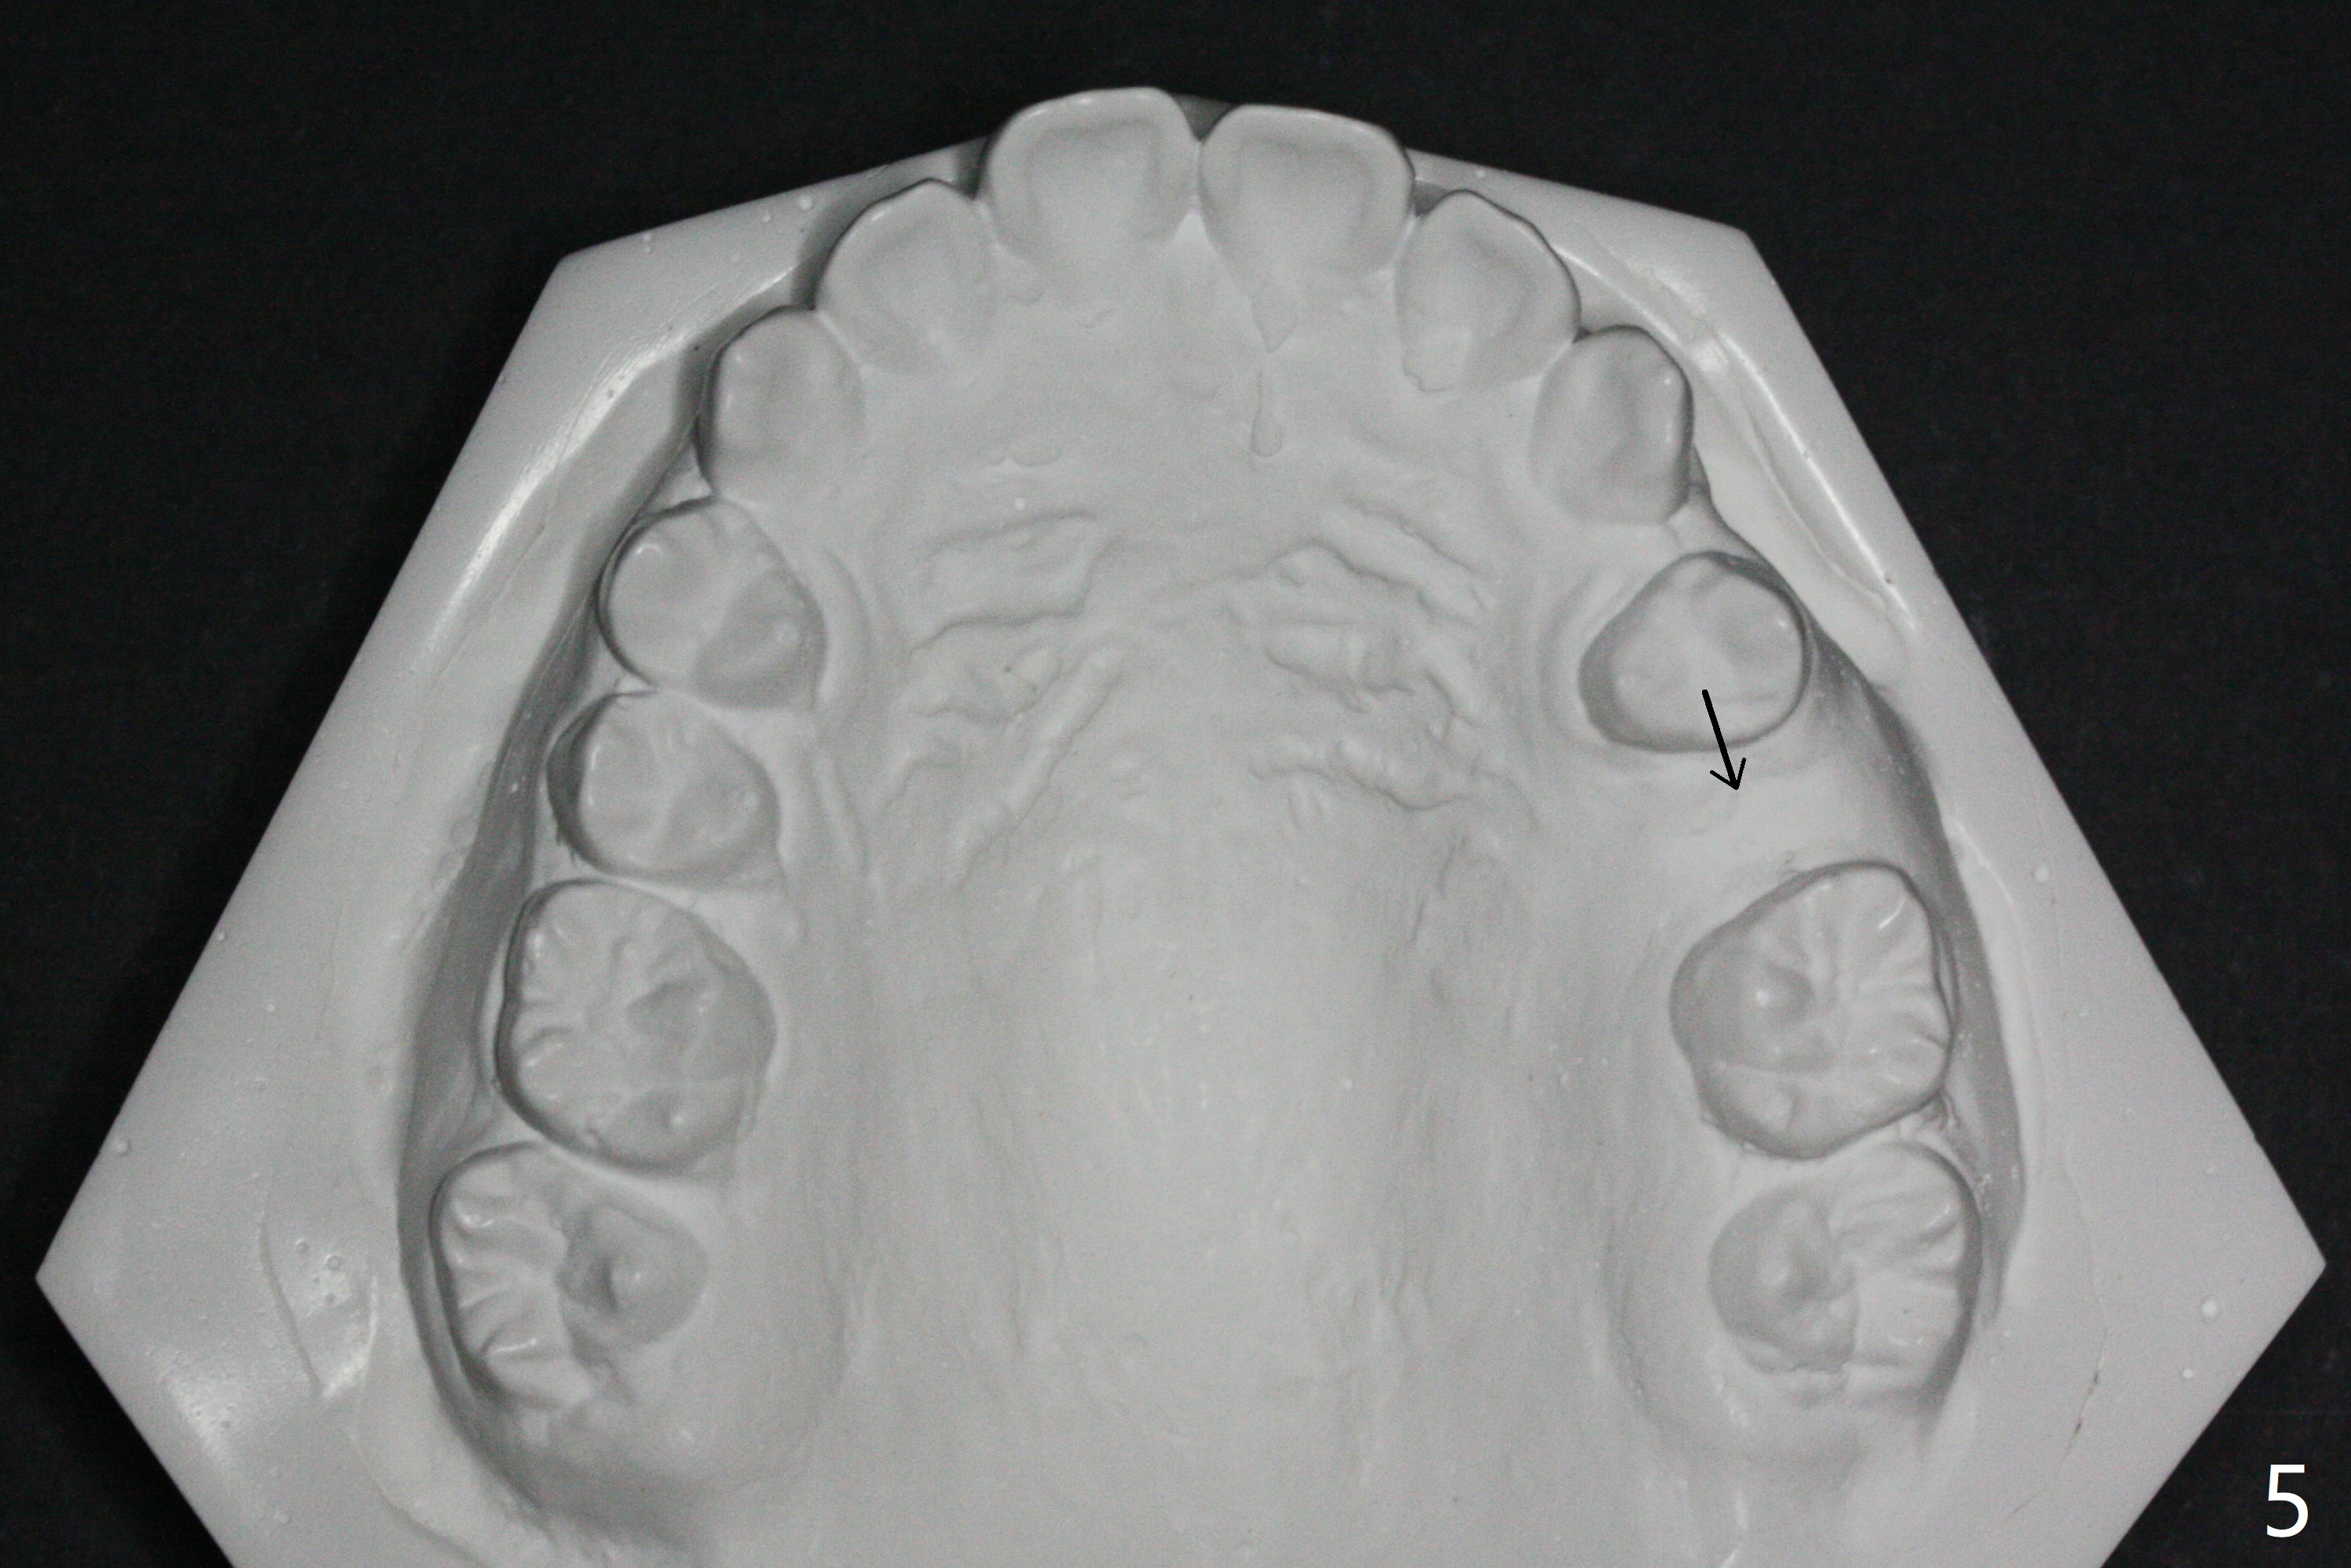

Pre-operative cephalometric X-ray shows convex facial profile (Fig.1). In fact tracing (a few days after banding) shows bimaxillary protrusion (SNA, SNB (88 and 87 degrees vs. 82, 80 (normal)). It appears that extraction orthodontics is indicated (UR4, UL5 (impacted) and LEs). The facial and upper dental midlines seem to coincide (Fig.2). No brackets or bands are placed at UR4 (because of non-cooperative (hyperactive)), LEs (Fig.3,4), or L7s (incomplete eruption, data not shown). Note wire bending between the canines and incisors, as related to correction of overbite. Shrinkable tubes are used in the region without bracket to prevent tissue injury. The upper arch seems to elongate (Fig.5, as compared to the lower one (Fig.6)). It appears that UR4 and UL5 should be extracted for normal profile and alignment. Cephalometric tracing shows that SNA and SNB are 79 and 85º, respectively, suggesting extraction (Fig.7).